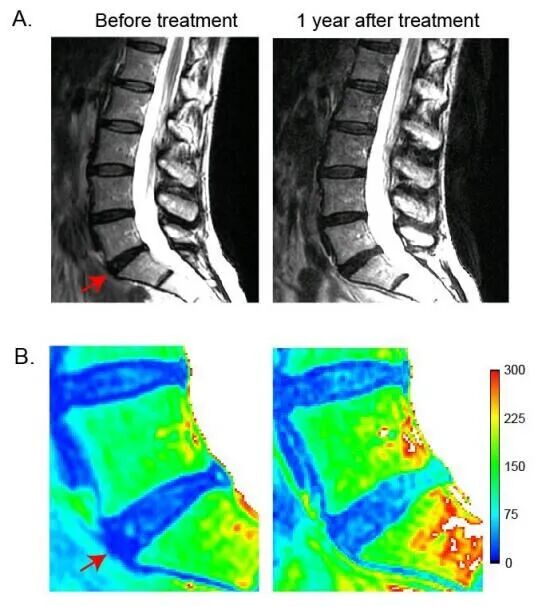

此外,研究者还发现,MSC治疗的患者中,Pfirrmann分级量化的退行性病变得到改善,而对照组却又恶化.

△ 间充质干细胞治疗后MRI变化